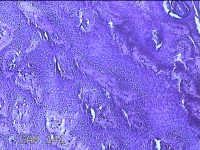

左侧臀部结节

性别

女

年龄

24岁

临床诊断

皮下结节

一般病史

发现左侧臀部结节1年余。

标本名称

大体所见

灰白暗红色带皮肤样结节0.7x0.3x0.2cm一个,表面糜烂,切开结节呈实性,切面灰白暗红色,质软。

图4